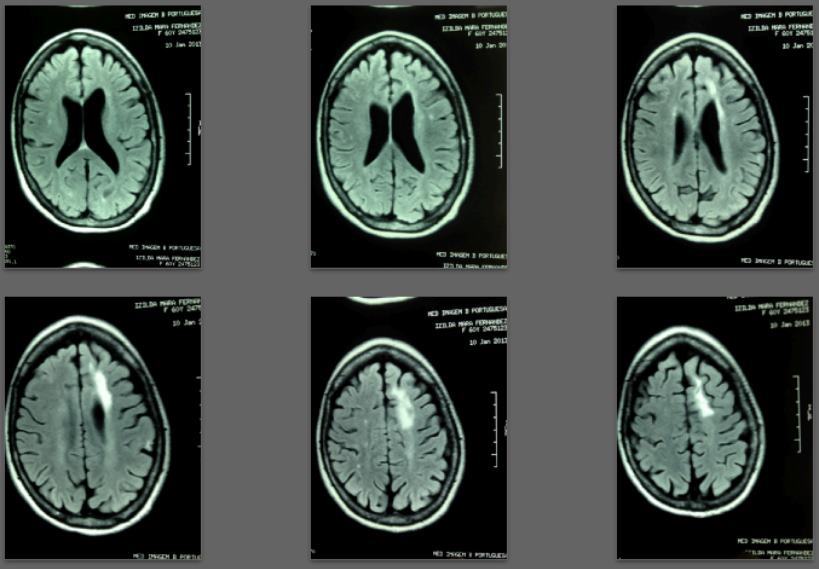

Specifically: Recent lesions appeared partially repaired or disappeared on MRI scans after one and two years of treatment.

Before/after MRI images for one of 1,000+ patients of Dr. Coimbra

PDF is attached at the bottom of this page

2008 Convulsive seizures Diagnosis: Balo’s concentric hemiparesis

Starting daily dose 25,000 IU; increased in stages to 80,000 IU on October 28, 2010. Asymptomatic since 2010.

2013 MRI